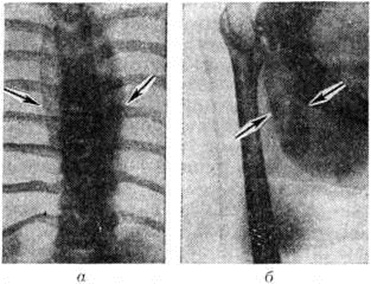

Рентгенологические выявляемость внутригрудных Натечник зависит от их локализации и величины, а Натечник, располагающихся вне грудной клетки, также от содержания в них извести и от вторичного смещения соседних органов. Следует различать прямые и косвенные рентгенологическое признаки Натечник К прямым признакам относятся чётко очерченные затемнения диаметром 2 сантиметров и больше, при внутригрудной локализации — сливающиеся с тенью позвоночника и контрастно выделяющиеся на фоне лёгких (рисунок 3, а). При иной локализации прямым признаком Натечник является затемнение, чаще продолговатой формы, резко очерченное с периферической стороны, с бледно-пятнистой, крапчатой или зернистой структурой в зависимости от степени обызвествления его содержимого (рисунок 3,6).

Косвенным признаком Натечник внелёгочной локализации может быть смещение смежных органов. Так, при локализации Натечник кпереди от шейных позвонков трахея на боковых рентгенограммах будет смещена кпереди. Располагаясь паравертебрально в поясничной области, Натечник ведёт к выпячиванию внешнего контура пояснично-подвздошной мышцы на большем или меньшем протяжении кнаружи с одной или обеих сторон; в норме этот контур прямолинейный или пологовыпуклый. Такое выпячивание может быть обусловлено не только давлением Натечник, но и специфическим псоитом (смотри полный свод знаний). При расположении в забрюшинном пространстве Натечник может сместить соседние органы: мочеточники, кишки и другие, что определяется при контрастном исследовании соответствующих органов.

К косвенным признакам Натечник, окружающего средние грудные позвонки, относится и деструкция главным образом передней поверхности тел этих позвонков, обусловленная пульсацией нисходящей части аорты, разрушающее действие которой передаётся на позвонки через жидкое содержимое Натечник При этом верхние и нижние края тел позвонков сохраняются дольше благодаря более резистентным выступающим межпозвоночным хрящевым дискам.

При увеличении в размерах или рассасывании Натечник тень его и степень смещения смежных органов меняются.

По мере затихания процесса, вызвавшего образование Натечник, содержимое последнего может подвергнуться обызвествлению. Тень Натечник вначале гомогенная, постепенно приобретает пятнистый, затем крапчатый рисунок вследствие нарастающего обогащения содержимого Натечник известковыми солями.

Форма Натечник определяется его размерами и средой, в которой он залегает, а также эластичностью его стенок. Так, при небольшой величине и внутригрудной локализации тень Натечник, более или менее симметрично окутывая тела позвонков, выпячивается в стороны в форме части шара. При большем распространении вдоль позвоночника тень Натечник из сферической может превратиться в овоидную и далее в цилиндрическую. При паравертебральном расположении Натечник, по форме близких к шару, овоиду или веретену (или части их), наибольший диаметр Натечник часто соответствует наиболее поражённому позвонку (перифокальный абсцесс). При локализации в клетчатке тень Натечник обычно имеет форму гладкого вытянутого овала с каплеобразно закруглённым дном; между мышцами овоидная тень Натечник заканчивается коническим заострением. Натечник может распространяться не только в силу тяжести вниз, но иногда и в краниальном направлении. Поэтому при спондилите нижних грудных позвонков рентгенологическое поиски Натечник следует проводить не только каудально, но и краниально; то же относится к коленному суставу и лонному сочленению.

Сам факт рентгенологическое выявления Натечник не всегда говорит об источнике и природе его; локализация и характер найденных при этом анатомических изменений костно-суставного аппарата (межпозвоночных дисков, костей, суставных хрящей и так далее), а также клинические, картина позволяют с большей уверенностью говорить об этиологии первичного заболевания скелета — туберкулёзной, кокковой, метатифозной, бруцеллезной, сифилитической, микотической и так далее Тень Натечник на рентгенограммах нередко требует дифференциальной диагностики (в зависимости от локализации) с так называемый сопутствующими позвоночнику тенями, с аневризмами аорты, опухолями лёгких, органов средостения, таза, лимфатических, узлов, мягких тканей шеи, грудной клетки, живота и конечностей, экстравазатами, гидронефрозом, дистопией и поликистозом почек, кистами и другие При осложнениях в течении Натечник, например, при прорыве в полость внутренних органов или наружу, необходимые диагностические уточнения могут быть получены с помощью соответствующих контрастных исследований.